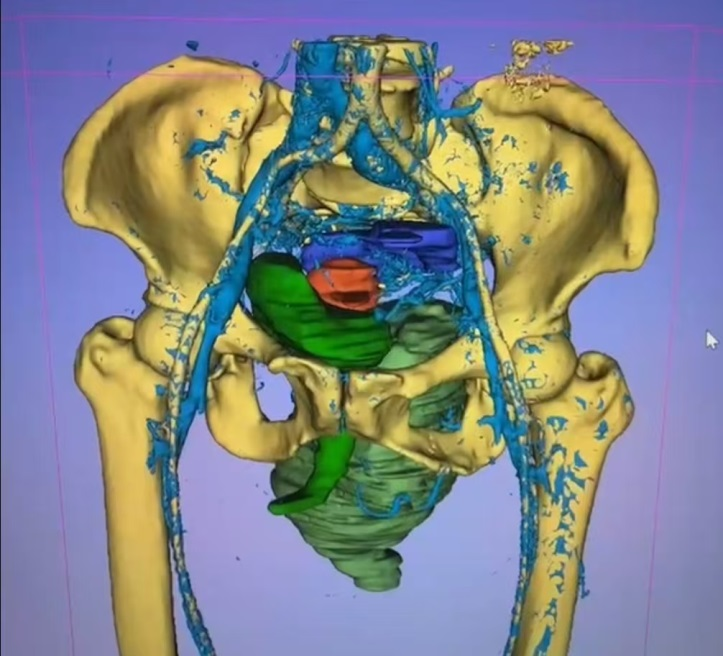

患者为54岁女性,自幼发现全身多发皮肤、皮下结节,并持续增多、变大,其中左臀部肿物尤为明显,因短时间内生长迅速、影响正常行走和排便功能来诊。患者体表可见大量散在皮肤结节、牛奶咖啡斑,MRI提示肿物信号混杂,膀胱、子宫、直肠明显受压右移,CT示该肿物跨盆腔内外,较大层面范围约13.5×8.7×13cm,密度欠均,夹杂囊变,累及左侧闭孔内肌、梨状肌、肛提肌及左侧外阴。

王伟东副主任团队根据患者临床症状、影像学特征及既往病史分析,确认患者得的是一种罕见遗传病——神经纤维瘤病1型(Neurofibromatosis type1,NF-1)。

经过与胃肠外科、泌尿外科、妇科等多学科专家讨论,决定对该肿物进行扩大切除术。该手术难点主要在于:1.肿瘤巨大,瘤体血供丰富,且临近骶静脉丛,出血风险极高;2.肿瘤与盆腔内脏器、髂血管、坐骨神经等重要结构关系密切。因肿物与直肠下段、肛门及阴道分界不清,肛提肌受累,需切除直肠下段及肛门行永久性造瘘,首先由我院胃肠外科团队完成腹腔镜下直肠、肛门切除术+结肠造口术。经过腹腔镜探查,泌尿外科、妇科团队确认肿物未累及膀胱、子宫等其他盆腔内脏器,由骨科团队在术前3d建模辅助下完成左臀部、盆底肿物扩大切除术。